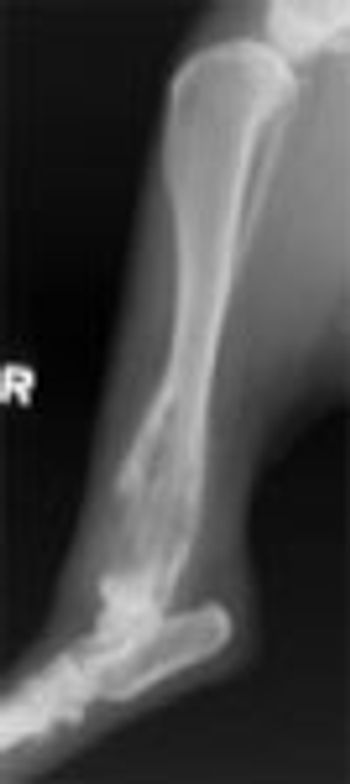

A 3-month-old Warmblood filly was referred to our hospital for evaluation of a left front-limb lameness of one week duration.

A useful protocol for practitioners who review their own films or send them to a specialist is to routinely obtain orthogonal views of the affected and normal bones.